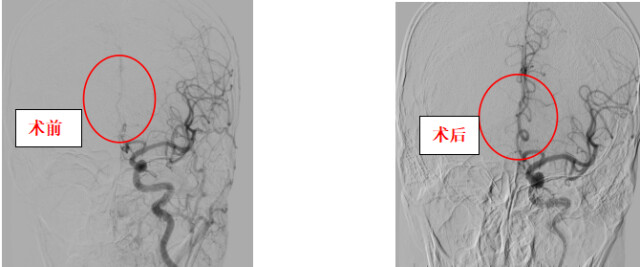

手术非常顺利,龚先生闭塞的大脑前动脉成功打通,术后血流恢复通畅,神志清醒,对答如流。

目前对于急性脑动脉闭塞,主要采用药物治疗和介入治疗等方式。介入治疗属于微创的手术方法,通过对脑部血管进行造影,显示出堵塞的血管;再利用动脉溶栓、支架取栓或抽吸导管等技术将堵塞血管开通,从而达到快速恢复脑组织血流供应,避免或减轻脑组织坏死的目的,具有创伤小、无痛苦、恢复快等特点。急性缺血性脑血管病患者在绿色通道模式下进行血管内介入治疗,可大幅缩短急诊救治时间,有效降低脑缺血再灌注损伤发生率。